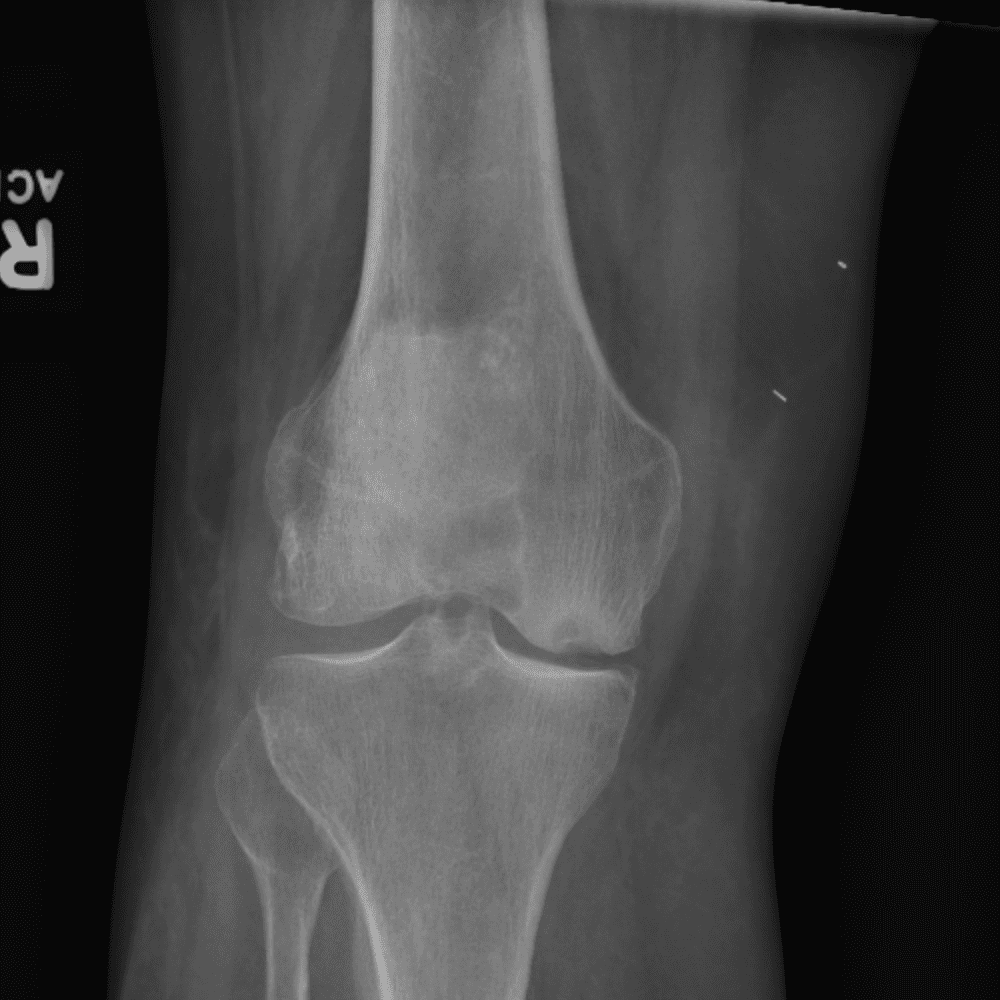

Simula o plantão incluindo casos sutis ou difíceis e alguns normais.